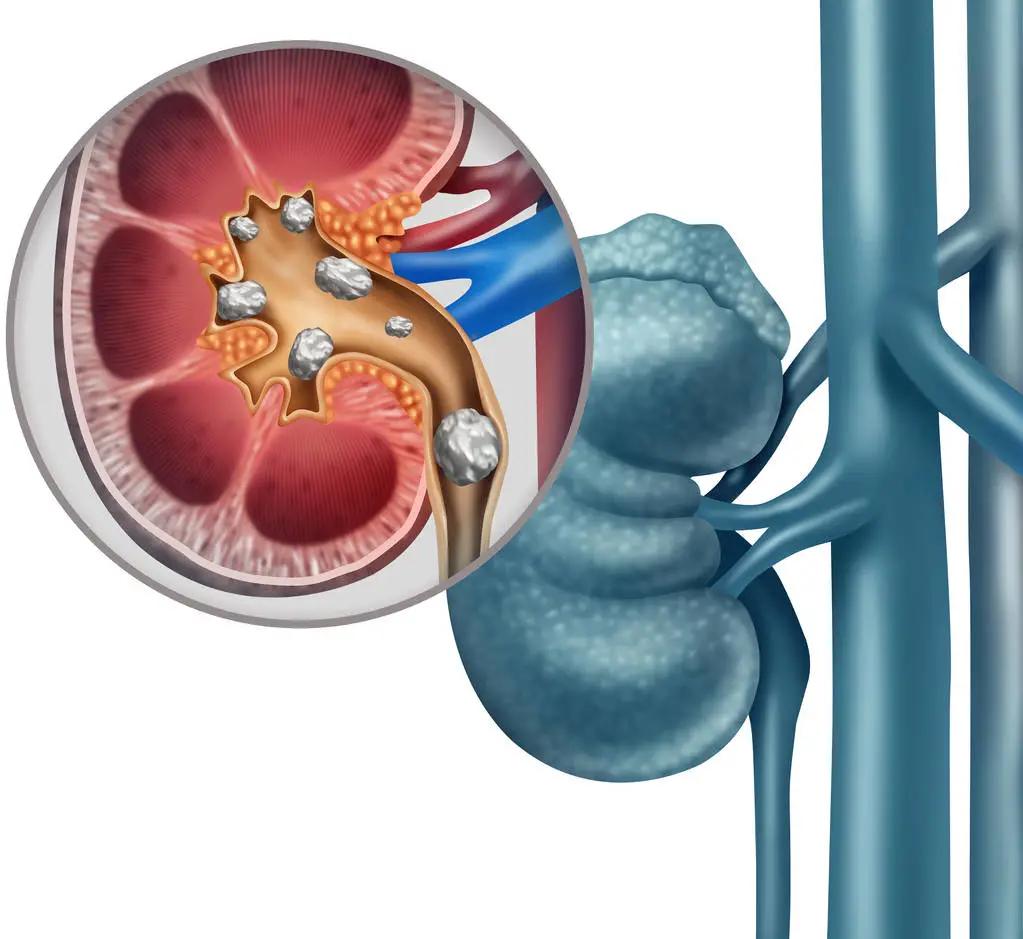

半月前因为又查出双肾结石

王主任啊,我右肾里有几个石头

你的左肾有结石、左输尿管也有结石

原来是王大妈的右肾结石掉了出来

形成右输尿管结石合并肾积脓,尿源性脓毒症

再加上王大妈左肾有结石且明显萎缩

双肾梗阻,同时发生了急性肾功能不全